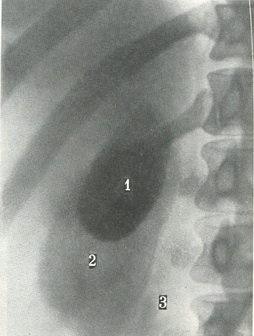

Холецистограммы можна отримати тільки після введення через травний тракт органічного контрастної речовини, куди входять сполуки йоду. Після всмоктування в кров препарати йоду виділяються з жовчю і концентрується в жовчному міхурі. Тінь міхура довжиною 5-8 см і шириною 2 - 3,5 см буває видно на знімку (рис. 271). При порушенні прохідності жовчних проток або присутності каменів тінь буде значно слабкіше. Проекція міхура залежить від конституції людини. У осіб гіперстенічного типу міхур знаходиться високо, а у астеніків може бути навіть в тазу, але це не є патологією.

![]() 271. Оглядовий передній знімок жовчного міхура при холецистографії. 1 - жовчний міхур; 2 - права нирка; 3 - зовнішній край великий поперекової м'язи.  |